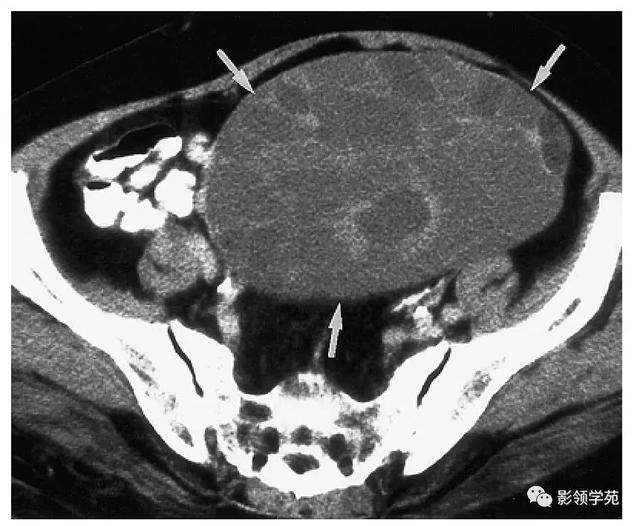

卵巢是女性重要的生殖器官,位于骨盆的深处靠近子宫的两旁,主要功能为制造卵子与女性荷尔蒙。很多人一听到肿瘤,就担心是不是「生了癌」;其实在妇科疾病中,卵巢肿瘤绝大部分属于良性,但范围却十分广泛,大致可区分成「生理性(功能性)囊肿」与「病理性囊肿」。

病理性囊肿通常是指卵巢产生的病变,但却不会自行消失,鄢源贵医师指出,这类肿瘤与卵巢的恶性肿瘤不易分辨,必须仰赖手术后的检查来做确认。病理性囊肿较常见的则有「子宫内膜异位瘤」(也就是所谓的巧克力囊肿)及「畸胎瘤」。「子宫内膜异位瘤」是指子宫内膜生长在子宫腔以外的地方,若长在卵巢内,便形成所谓的巧克力囊肿,由于它会破坏女性生殖系统,又易转移、复发、难以痊愈,因此容易影响女性受孕功能。至于畸胎瘤,则好发在生育年龄的年轻女性群,由于在临床上并没有特殊症状,因此很难发现。

畸胎瘤是年轻女性最常出现的良性卵巢肿瘤,很多人以为卵巢畸胎瘤跟怀孕有关,其实不然,鄢源贵医师解释,由于胚胎发育时期,有一部分的生殖细胞在移行过程中迷路,这些细胞因为不明原因衍生分化成类似胚胎的组织,留存在畸胎瘤中,出现类似皮肤的构造,所以也有人称为「皮样囊肿」。良性畸胎瘤约占卵巢肿瘤的10%,但有约2%的畸胎瘤会产生恶性病变,但通常都只是单侧发生,两侧发生的概率约为10~15%。